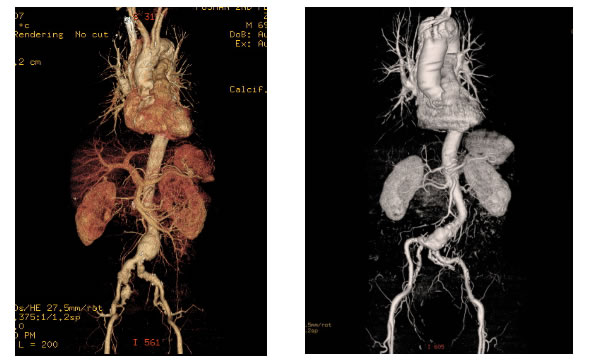

随即,两位患者转入甲状腺疝气小儿外科并完善术前的胸腹血管CT检查。黄文分析CT后,决定行介入手术—腹主动脉瘤腔内隔绝术治疗。

黄文主任介绍,腹主动脉瘤的形成是因为动脉中层结构破坏,动脉壁不能承受血流冲击的压力而形成的局部或者广泛性的永久性扩张或膨出,多于查体或腹部影像学检查中发现,其主要症状为腹部的搏动性肿物、腰腹部疼痛等。由于致死率高,明确患有腹主动脉瘤的患者必须严格随诊观察动脉瘤的大小变化,尽早手术治疗防止动脉瘤的破裂。传统的开刀手术治疗腹主动脉瘤创伤巨大、耗时长、并发症多、术后恢复慢,但随着介入手术的发展和进步,腔内隔绝治疗腹主动脉瘤已经逐渐成为治疗腹主动脉瘤的主流手术。手术全程在血管腔内进行,术后仅留下1-2mm的穿刺伤口,手术耗时更快、更微创、术后恢复时间大大缩短。